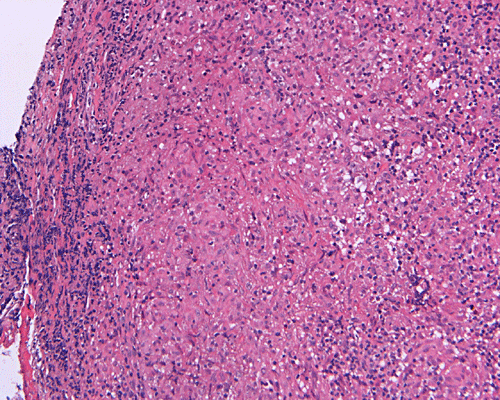

Paraffin sections: The entire volume of the tissue is made up of a granulomatous inflammation with poorly formed granuloma (Panel F, G, and H). The density of the lymphocytes is variable in different areas. In some areas, there is a rather intense lymphocytic infiltration accompanied by scant atypical cells with enlarged nulcei and prominent nucleoli (arrows in Panel I and J, Panel J is a higher magnification of Panel I). These atypical cells are quite easy to be missed. No microorganisms were identified by acid fast stain, PAS stain or GMS stain. The lymphocytes but not the atypical cells are positive for CD20 (Panel K) or CD3 (Panel L). The granulomatous background is strongly positive for CD68 (Panel M). Only rather faint positive staining for placental alkaline phosphatase (PLAP) is demonstrated and the interpretation is difficult as they are present in areas with crush artifact (Panel N). Many of the large, atypical cells are positive for CD117 (c-kit) (Panel O).

Intracranial germinoma is histologically identical to ovarian dysgerminoma and testicular seminoma. There is a tendency to infiltrate adjacent structures and to spread throughout the ependyma, the ventricular system and subarachnoid spaces. Microscopically, they consist of nests, lobules, cords, and/or sheets of large round tumor cells with well-defined borders, clear to pale cytoplasm with artifactual vacuolization, round and centrally located nuclei with open chromatin and prominent round or bar-shaped nucleoli. The cytoplasm is glycogen-rich, making these cells periodic acid-Schiff (PAS)–positive and diastase sensitive. These tumor cells are mitotically active. Atypical mitosis, however, is not a common finding. Necrosis is usually not prominent. In the most classic histologic picture, clusters and cords of large germinoma cells are separated by a dense, lymphocytic infiltration admixed with some macrophages and a delicate fibrovascular network. Plasma cells may be found. At medium-power magnification with hematoxylin and eosin stain, the contrast between the smaller, darkly staining lymphocytes and the larger, pale staining cytoplasm of neoplastic cells is virtually pathognomonic. The amount of inflammatory cells can have wide variations among different tumors. In some occasions, the large germinoma cells are difficult to be found and the overall picture may suggest a lymphoma. Syncytiotrophoblastic cells can also be present. These cells should not be mistaken as evidence of choriocarcarcinoma.

Germinomas can elicit an atypical gliosis in the surrounding glial tissue which may be confused with malignant glial neoplasms. This is true particularly of specimens taken from the periphery of the germinoma. The tumor may appear as a desmoplastic tumor. The inflammatory response may be problematic in reaching a histologic diagnosis, especially in small biopsies, as macrophages can be difficult to distinguish from a non-seminomatous neoplastic component.

Granulomatous changes are common findings in germinomas and intracranial germinomas follow this general trend 3, 4, 5. It can be extensive. This feature is particularly problematic in neuropathologic when stereotactic biopsy is performed and the amount of tissue available for examination is limited as illustrated in this case. During intraoperative consultations, a frozen section diagnosis of granulomatous inflammation should prompt additional sampling as isolated granulomatous inflammation of infectious origin and sarcodosis are quite uncommon in the pineal gland.